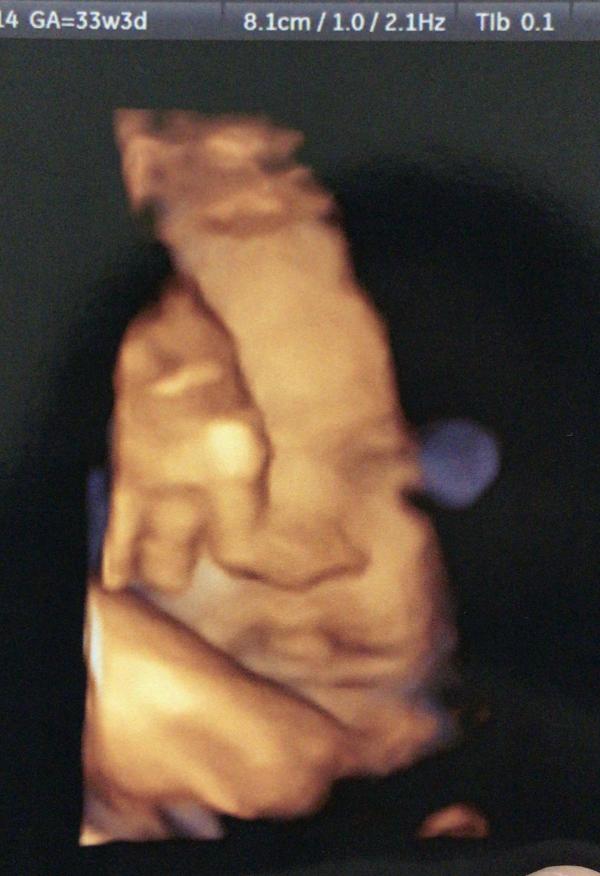

С какой недели можно делать его чтоб так же четко видеть малыша

@m05ru241, с 22 недели тоже чётко видно бывает , ну смотря как малыш покажет личико🤗